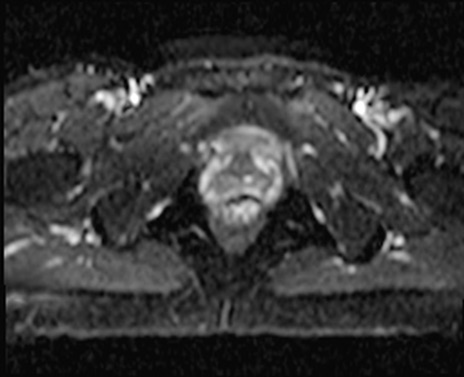

MRI(4日後)